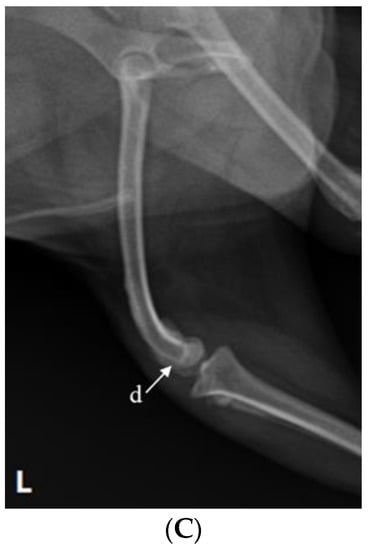

Figure 4.

Radiograph images depicting the stifle joint arthrodesis performed on the right hind limbs and the medial patellar luxation correction of the left hind leg. (A) Craniocaudal radiographic view of both stifle joints. (B) Mediolateral radiographic view of stifle joints following SJA. (C) Postoperative mediolateral view of MPL in the left hindlimb.

2.4. Reconstruction of MPL

After performing SJA of the right hind limb, MPL correction of the left hind limb was performed. The approach was carried out by making a vertical incision of about 10 cm in the craniolateral parts around the stifle joint. After the fascia and articular capsule were incised to expose the trochlea of the femur, tracheoplasty was performed in a wedge shape to secure the depth of the trochlea. Then, the wedge-shaped articular cartilage was inserted into the femoral trochlea. Subsequently, a tibial tuberosity that had moved toward the inside was cut using a bone saw and moved laterally to fit the patella into the trochlear groove using a K-wire (Figure 4A,C). Stability was further enhanced using the figure-of-eight-tension-band-wiring technique. Before suturing, the distal tibia was rotated internally and externally 2–3 times to confirm that the patella (Figure 4A,C) remained stable in the newly formed trochlear groove. Subsequently, routine closure was performed in the following order: joint capsule, muscle, subcutaneous tissue, and skin.